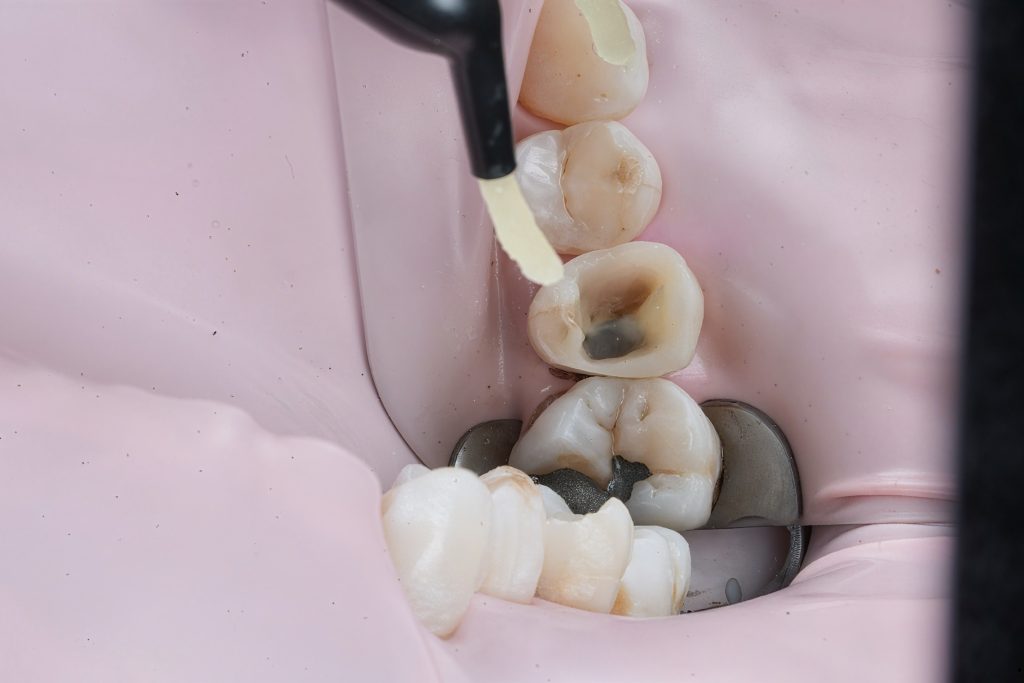

Rubber dam isolation achieved using clamp stabilization to maintain a dry and clean operative field – essential for adhesive dentistry (Fig 1–2).

Defective composite and caries were removed in a controlled manner preserving sound enamel walls. Teflon floss ties and wooden wedges used for separation and gingival retraction (Fig 3–6).

3. Matrix System Placement

Sectional matrix system used to recreate anatomical proximal walls. Ring stabilization applied to ensure tight contact and optimal emergence profile (Fig 7–8).

- Initial caries exposure and removal

- Proximal clearance and wedge placement

- Matrix placement and isolation refinement

- Sectional ring application